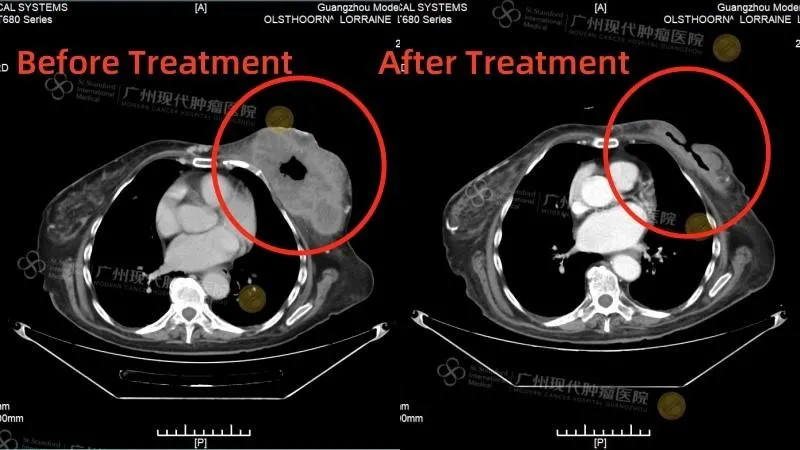

История пациента: Лоррейн, 61 год, Австралия. Диагноз: Плоскоклеточный рак молочной железы (T4N2M1), поздняя стадия с изъязвлением и кровотечением. Тактика лечения: Эмболизация опухолевых сосудов и внутриартериальная химиотерапия. Результат: После двух процедур достигнута регрессия опухоли на 60%, восстановлена мобильность и улучшено качество жизни.

К моменту госпитализации в феврале 2025 года состояние Лоррейн было крайне тяжелым. Огромная изъязвленная опухоль размером 14х8х14 см вызывала кровопотерю, требовавшую частых переливаний. Из-за болезни она потеряла 30 кг и практически не могла передвигаться. Мультидисциплинарная команда врачей провела углубленную диагностику и немедленно приступила к работе. Первым шагом стала стабилизация общего состояния: коррекция работы почек и сердца. После этого Лоррейн прошла два сеанса эндоваскулярного лечения - артериальной химиоэмболизации.

Результат, вернувший веру Эффект от лечения превзошел ожидания.

После двух процедур опухоль уменьшилась на 60%, что позволило остановить кровотечение и значительно улучшить самочувствие Лоррейн. Она не только встала на ноги, но и вернула себе самостоятельность.

«Я счастлива, что настояла на своем. Здесь мне не только подарили шанс на жизнь, но и подробно объяснили каждый шаг лечения. Персонал невероятно внимателен и профессионален. Я хочу верить в полное выздоровление и надеюсь, что моя история придаст сил другим пациентам не сдаваться и искать возможности», - говорит Лоррейн. Контрольное обследование в апреле 2025 года подтвердило стойкую положительную динамику. История Лоррейн - это пример того, как вера в современную медицину и готовность к решительным шагам способны победить даже самый сложный диагноз.